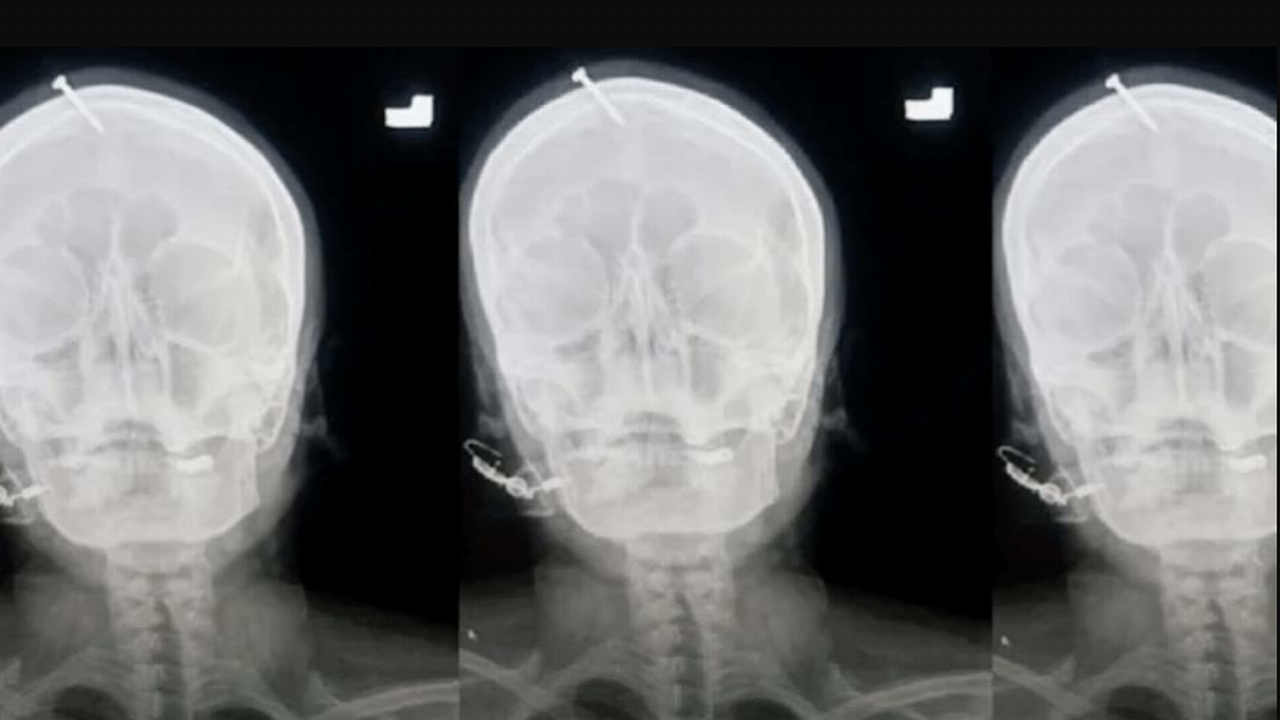

Pakistan'da hamile bir kadın, dördüncü bebeğinin erkek olması için kafasına 5 santimlik çivi çaktırdı.

Polis tarafından henüz kimliği belirlenemeyen kadın, bu hafta Pakistan’daki Lady Reading Hastanesine kafatasından yoğun kanama ile geldi. İlk başta Peşaver şehri sağlık personeline, doğmamış çocuğunun cinsiyetinin erkek olmasını garantilemek için ilahiler okumasının ve kendi kafasına çivi çakmasının tavsiye edildiğini söyledi.

Hastanedeki beyin cerrahı Haider Suleman yerel basına, kadının kanaması olduğunu ve geldiğinde çok acı çektiğini, ancak aklının yerinde olduğunu söyledi. Doktor, gazetecilere verdiği demeçte olayla ilgili şunları söyledi: “Yöresindeki bir kadının, bir çiviyi kafasına saplayarak ultrasonda kız görünmesine rağmen bir erkek çocuk doğurduğunu söyledi. Doktorlar ameliyat ile çiviyi çıkarabildiler.”

Hastaneye gelen kadının olağan dışı kafa travmasının görüntüleri internette hızla yayıldı. Görüntüler üzerine harekete geçen polis, şimdi şifacı olduğunu iddia eden ve bu yaralanmaya neden olan kadını arıyor.